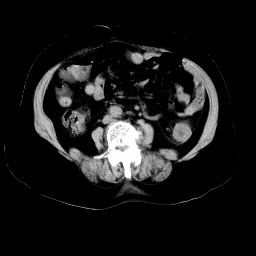

以下是引用余辉在2008-11-9 9:47:00的发言:[br]各层面均可见降结肠管壁增厚,管腔狭窄,中部层面可见管壁明显增厚区,结合病史多考虑降结肠癌,溃疡性结肠炎不除外,建议进一步检查